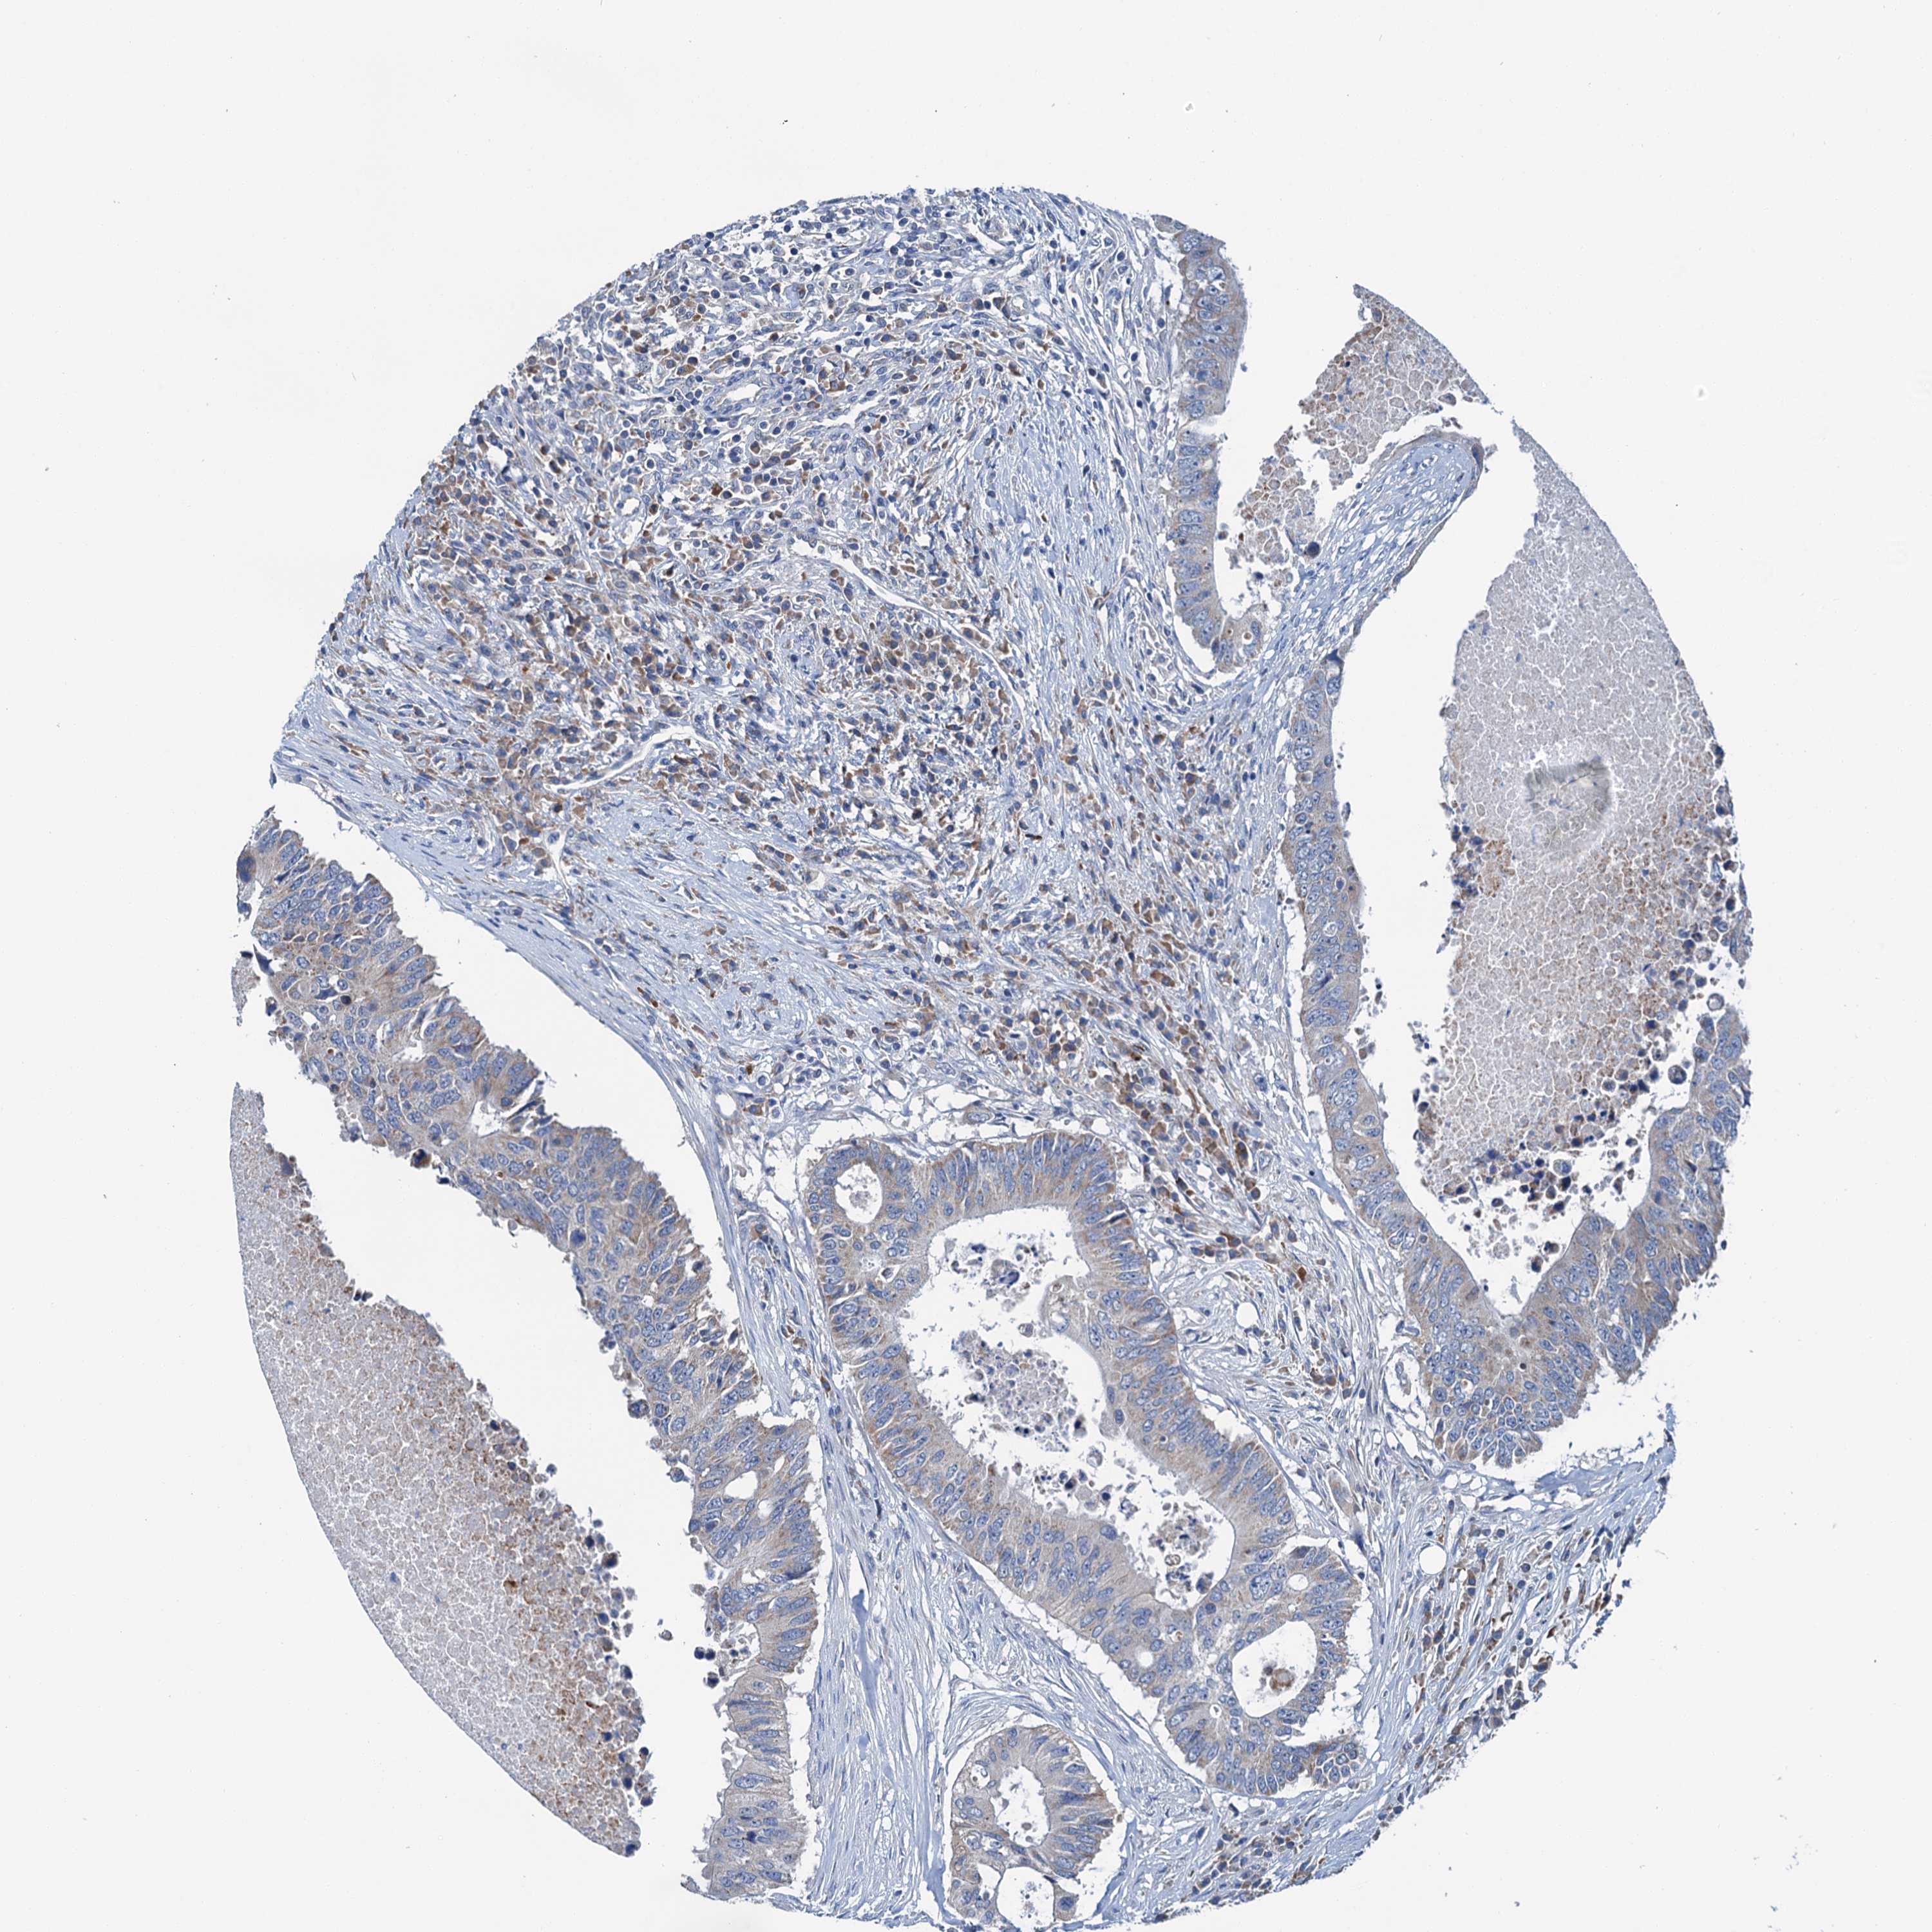

CANCER COLORECTAL CANCER Show tissue menu

Colorectal cancer

Human cancer

Colon adenocarcinoma